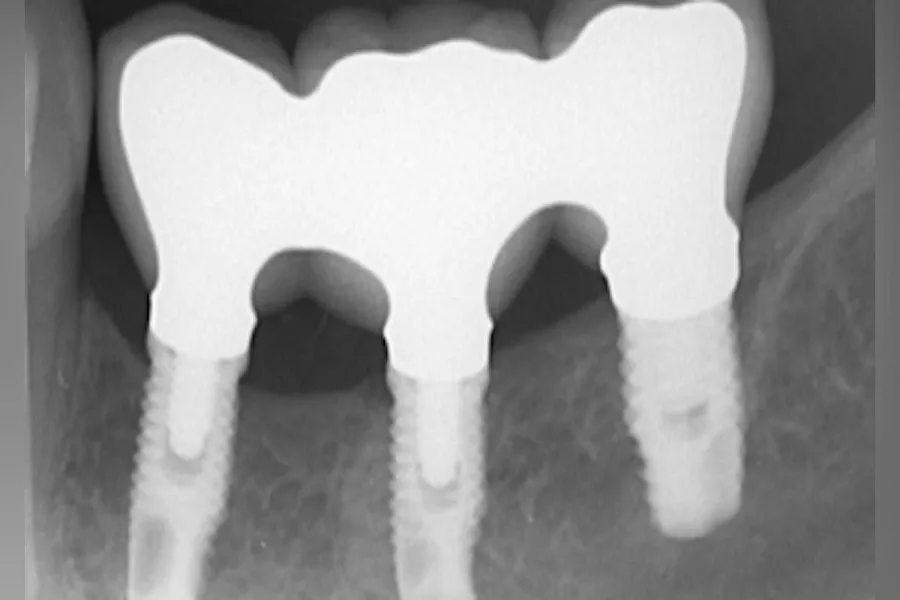

Dental caries, loose residual teeth, misalignment of adjacent teeth, deviation of the opposite teeth and periodontal disease are the most common complications of tooth loss. These symptoms will bring irreversible damage to oral health, followed by digestive system diseases. In addition, many clinical data show that chronic diseases frequently encountered in middle-aged and elderly people, such as diabetes, coronary heart disease, Alzheimer’s disease, etc., are related to oral health. Are dental implants safe? Dental implants are also called artificial dental implants. They are not really planted with natural teeth, but are made of pure titanium metal with high bone compatibility through medical methods. shape. It is surgically implanted into the alveolar bone of the edentulous area. After 3-4 months, when the artificial tooth root is tightly combined with the alveolar bone, a porcelain crown is made on the artificial tooth root. Rising in developed countries in Europe and the United States, it is now a very mature method for missing teeth.??

Experts say that dental implants are currently the world’s best recognized technology for restoration of missing teeth, and half-oral teeth can also be repaired through dental implants. So, what is the effect of half-mouth implants? Experts say that if you have a good dental implant effect, you should follow the doctor’s doctor’s advice for dental implant care.??

Experts say that you must pay attention to the maintenance of dental implants after surgery to achieve good results. After the success of dental implants, the performance of its effect mainly depends on the care of consumers in daily life. First of all, it is necessary to do good oral hygiene. Secondly, it is important to have regular follow-up visits. Regular follow-up visits are not only a comprehensive evaluation of the oral cavity and dental implants, but also a repair and improvement of dental implants. The effect of dental implants is very good, not only can restore oral function, but also more beautiful, the service life of dental implants is generally more than ten years, if the dental implants are protected, dental implants can accompany us for life